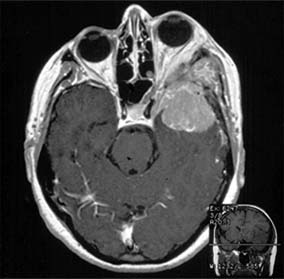

Primary optic nerve sheath meningioma is a rare tumor most commonly presenting, like other types of meningioma, in middle-aged women (Figure 14-19). Five percent of cases are bilateral. Visual loss is slowly progressive. The classic clinical features are a pale, slightly swollen optic disk with retinochoroidal collaterals, but in most cases the collateral vessels are not present (new window  Figure 14-6). Surgical excision invariably leads to complete loss of vision and is generally reserved for blind eyes to prevent intracranial spread of tumor. Focal radiotherapy is becoming more popular.

Figure 14-19

Figure 14-19: MRI of tubular optic nerve sheath meningioma.